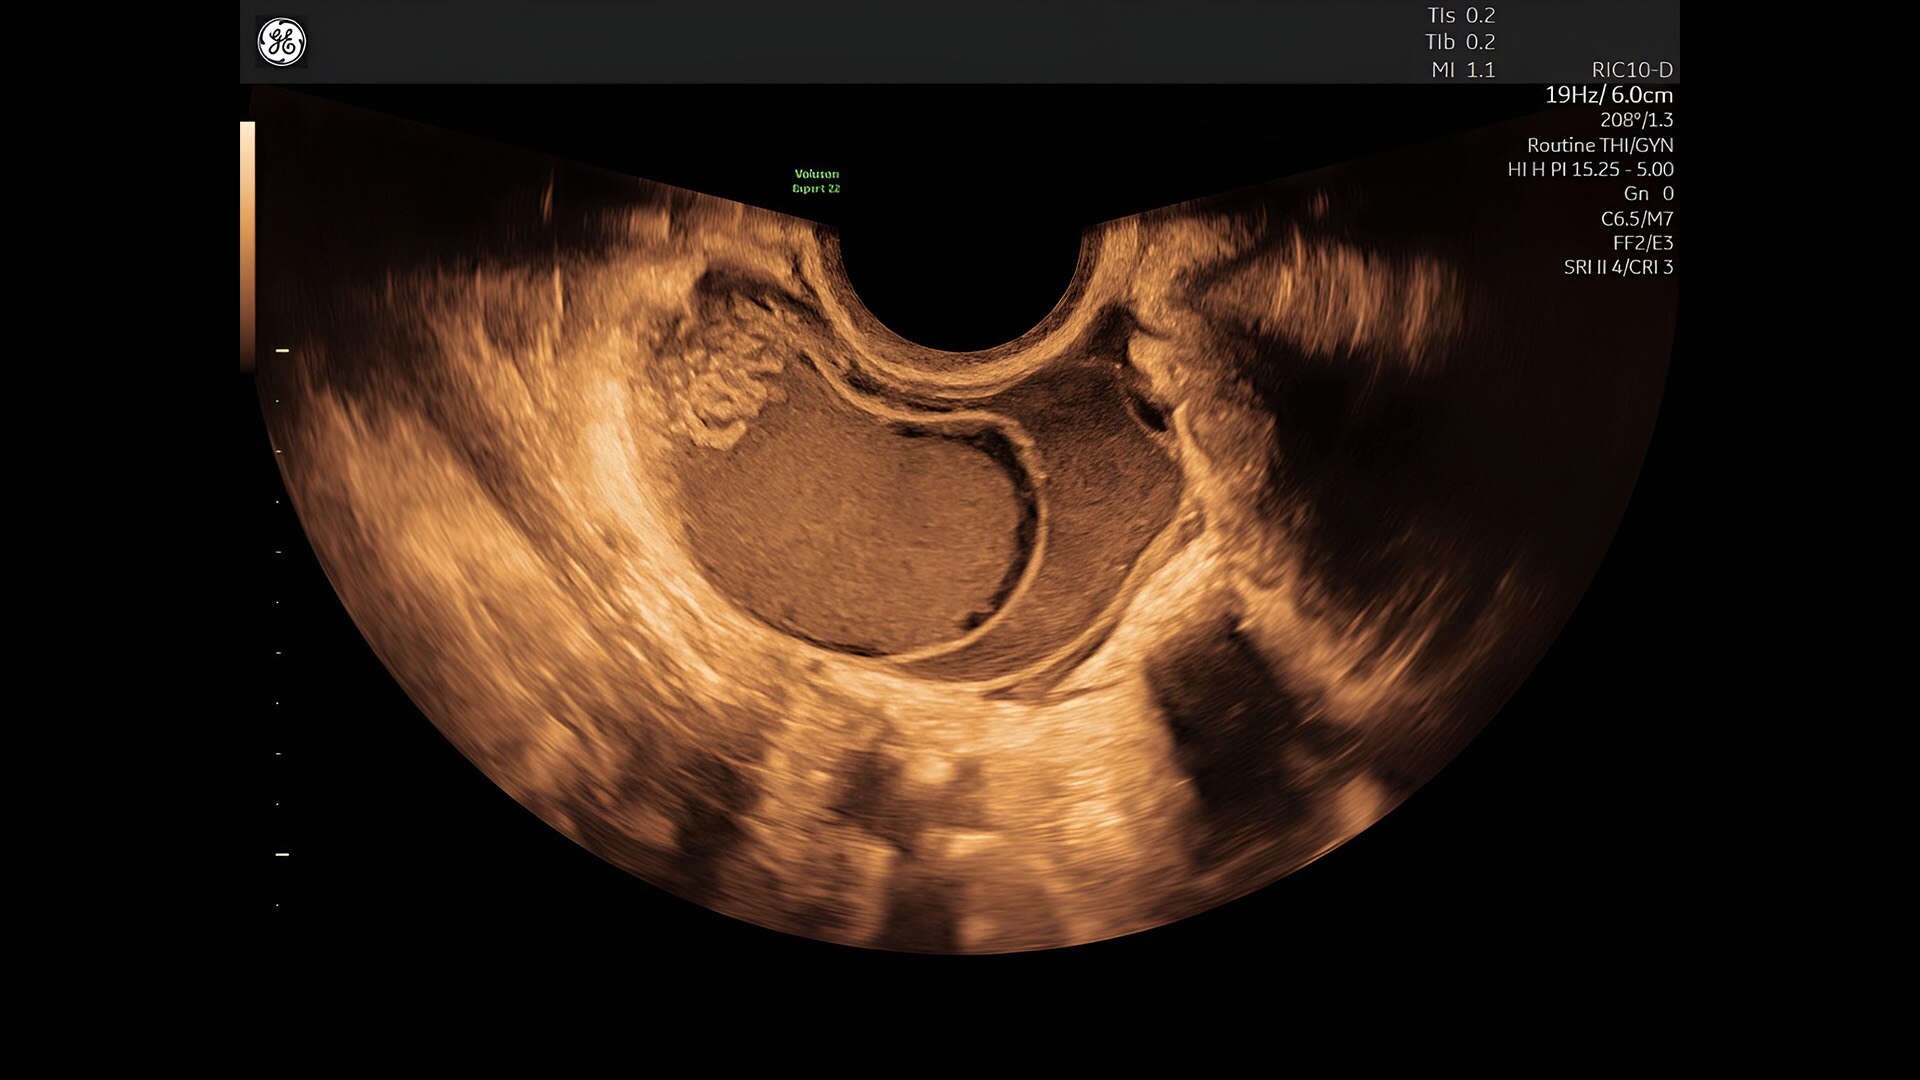

Discover complicated anomalies and pathologies with the Voluson Expert 22 to provide answers sooner for better decision making.

Complex cases come with enough uncertainty. That's why the Voluson Expert 22 is specifically designed for in-depth assessment of complicated anatomy — with pioneering first trimester, fetal cardiac, gynecological, and other pivotal technologies that focus on early detection and intervention.